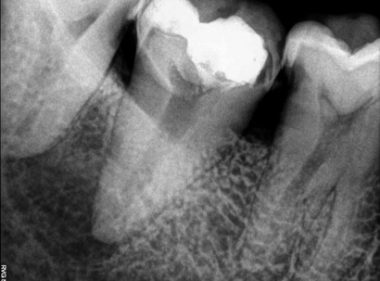

Patient Name:Rakesh Sinha

Tooth Involved :46

Diagnosis :Distocclusal Caries Involving Enamel And Dentin

Treatment :Indirect Restoration With Cuspal Coverage Of Distocclusal Cusp